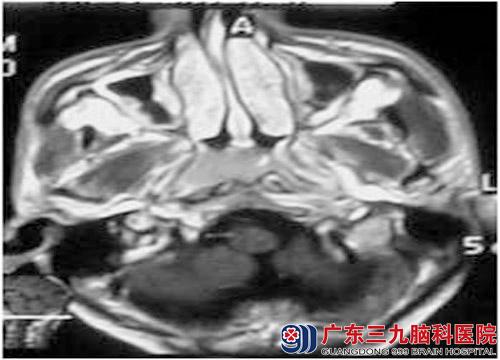

关先生今年46岁,为货车司机。2009年2月出现左侧颈部肿物,伴回涕带血,来广东三九脑科医院治疗。鼻咽镜活检病理为非角化未分化型癌,头颅MR示鼻咽部肿物,诊断鼻咽癌。查体左侧颈部二腹肌下及中颈部可触及肿大淋巴结,直径分别约62.5px、50px,右侧中颈也可触及肿大淋巴结,直径约12.5px。2009年2月先行诱导化疗1周期,化疗后行鼻咽及颈部放疗,鼻咽部放疗72Gy/36f,颈部完成60Gy/30f。同期行4次同步化疗,同步放化疗后行辅助化疗四周期。目前治疗后五年余,精神、反应良好, 鼻咽部MRI结果回报未见肿瘤复发。预后评价为临床治愈。目前正常生活工作。

放疗前

放疗后

放疗5年后